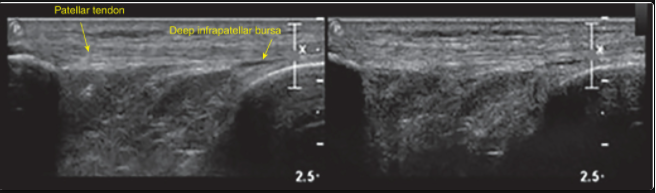

Name the 3 components of spatial resolution in ultrasound?